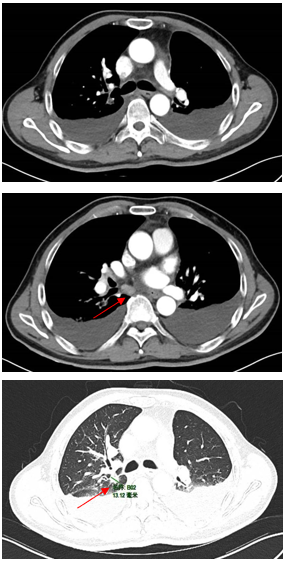

胸部CT显示左侧上叶支气管旁部发现一不规则、边界不清的软组织肿块,大小约为41mm×26mm。增强扫描后,肿瘤呈显著不均匀强化,与肿大的淋巴结粘连且难以区分,部分包裹左上叶支气管,导致管腔狭窄。左上叶肺叶间裂增厚,多个结节灶提示可能存在肺内转移。

新辅助治疗:SBRT方案的剂量为24Gy/3次(每次8Gy),连续3天完成;靶区为仅针对原发肿瘤(GTV),未照射淋巴结;PTV中位体积为152cc(范围20–584cc);化疗方案(每3周一次)为紫杉醇274mg(第1天),顺铂40mg(第1–3天);免疫治疗为替雷利珠单抗(PD-1抑制剂)200mg(第1天,每3周)。

治疗缓解评估:影像学(CT)显示原发肿瘤及叶间淋巴结明显缩小;支气管镜显示左上叶开口通畅,原肿块显著退缩,可见白色坏死组织;疗效评估为PR。

术后病理结果:鳞状细胞癌;残留肿瘤细胞为5%;间质成分(纤维化/炎症)为90%;淋巴结为0/13转移;ypT1aN0M0,IA期;疗效评估为MPR。